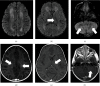

The raccoon roundworm Baylisascaris procyonis (B. procyonis) may infect humans to cause severe or fatal meningoencephalitis, as well as ocular and visceral larva migrans. Young children are at greater risk for cerebral larva migrans with severe meningoencephalitis, and early empiric therapy may improve outcomes. Familiarity with characteristic brain imaging findings may prompt earlier diagnosis, particularly in the setting of CSF eosinophilia. We report a case of a 19-month-old boy who presented with truncal ataxia and was found to have peripheral and CSF eosinophilia. MRI demonstrated symmetric, confluent T2 hyperintense signal in the cerebral and cerebellar deep white mater, which helped differentiate B. procyonis meningoencephalitis from other infectious and non-infectious causes of eosinophilic meningoencephalitis. Early recognition and treatment of B. procyonis meningoencephalitis are important for improved outcomes, and careful review of neuroimaging can play a critical role in suggesting the diagnosis.